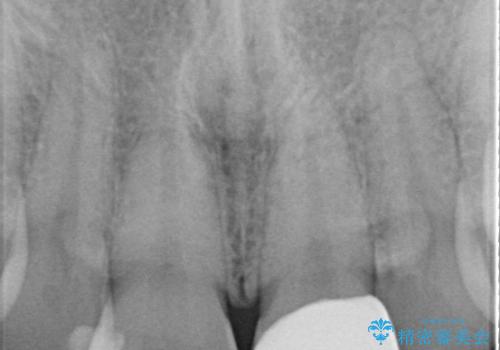

- 定期的に当院に通院されている患者様ですが、前歯が欠けてしまい困っているとのことで来院されました。その日は応急でレジン充填を行いましたが、上下顎前歯の当たりが強くまた同じように欠けてしまう可能性が高いと考え、セラミッククラウンにて修復した一例です。前歯一歯の色合わせは非常に難しく、特に周囲の歯に模様がある場合難易度が上がります。そのため、今回は当院のセラミッククラウンの中で最もランクの高いものを選択し、非常に綺麗に仕上げることができました。